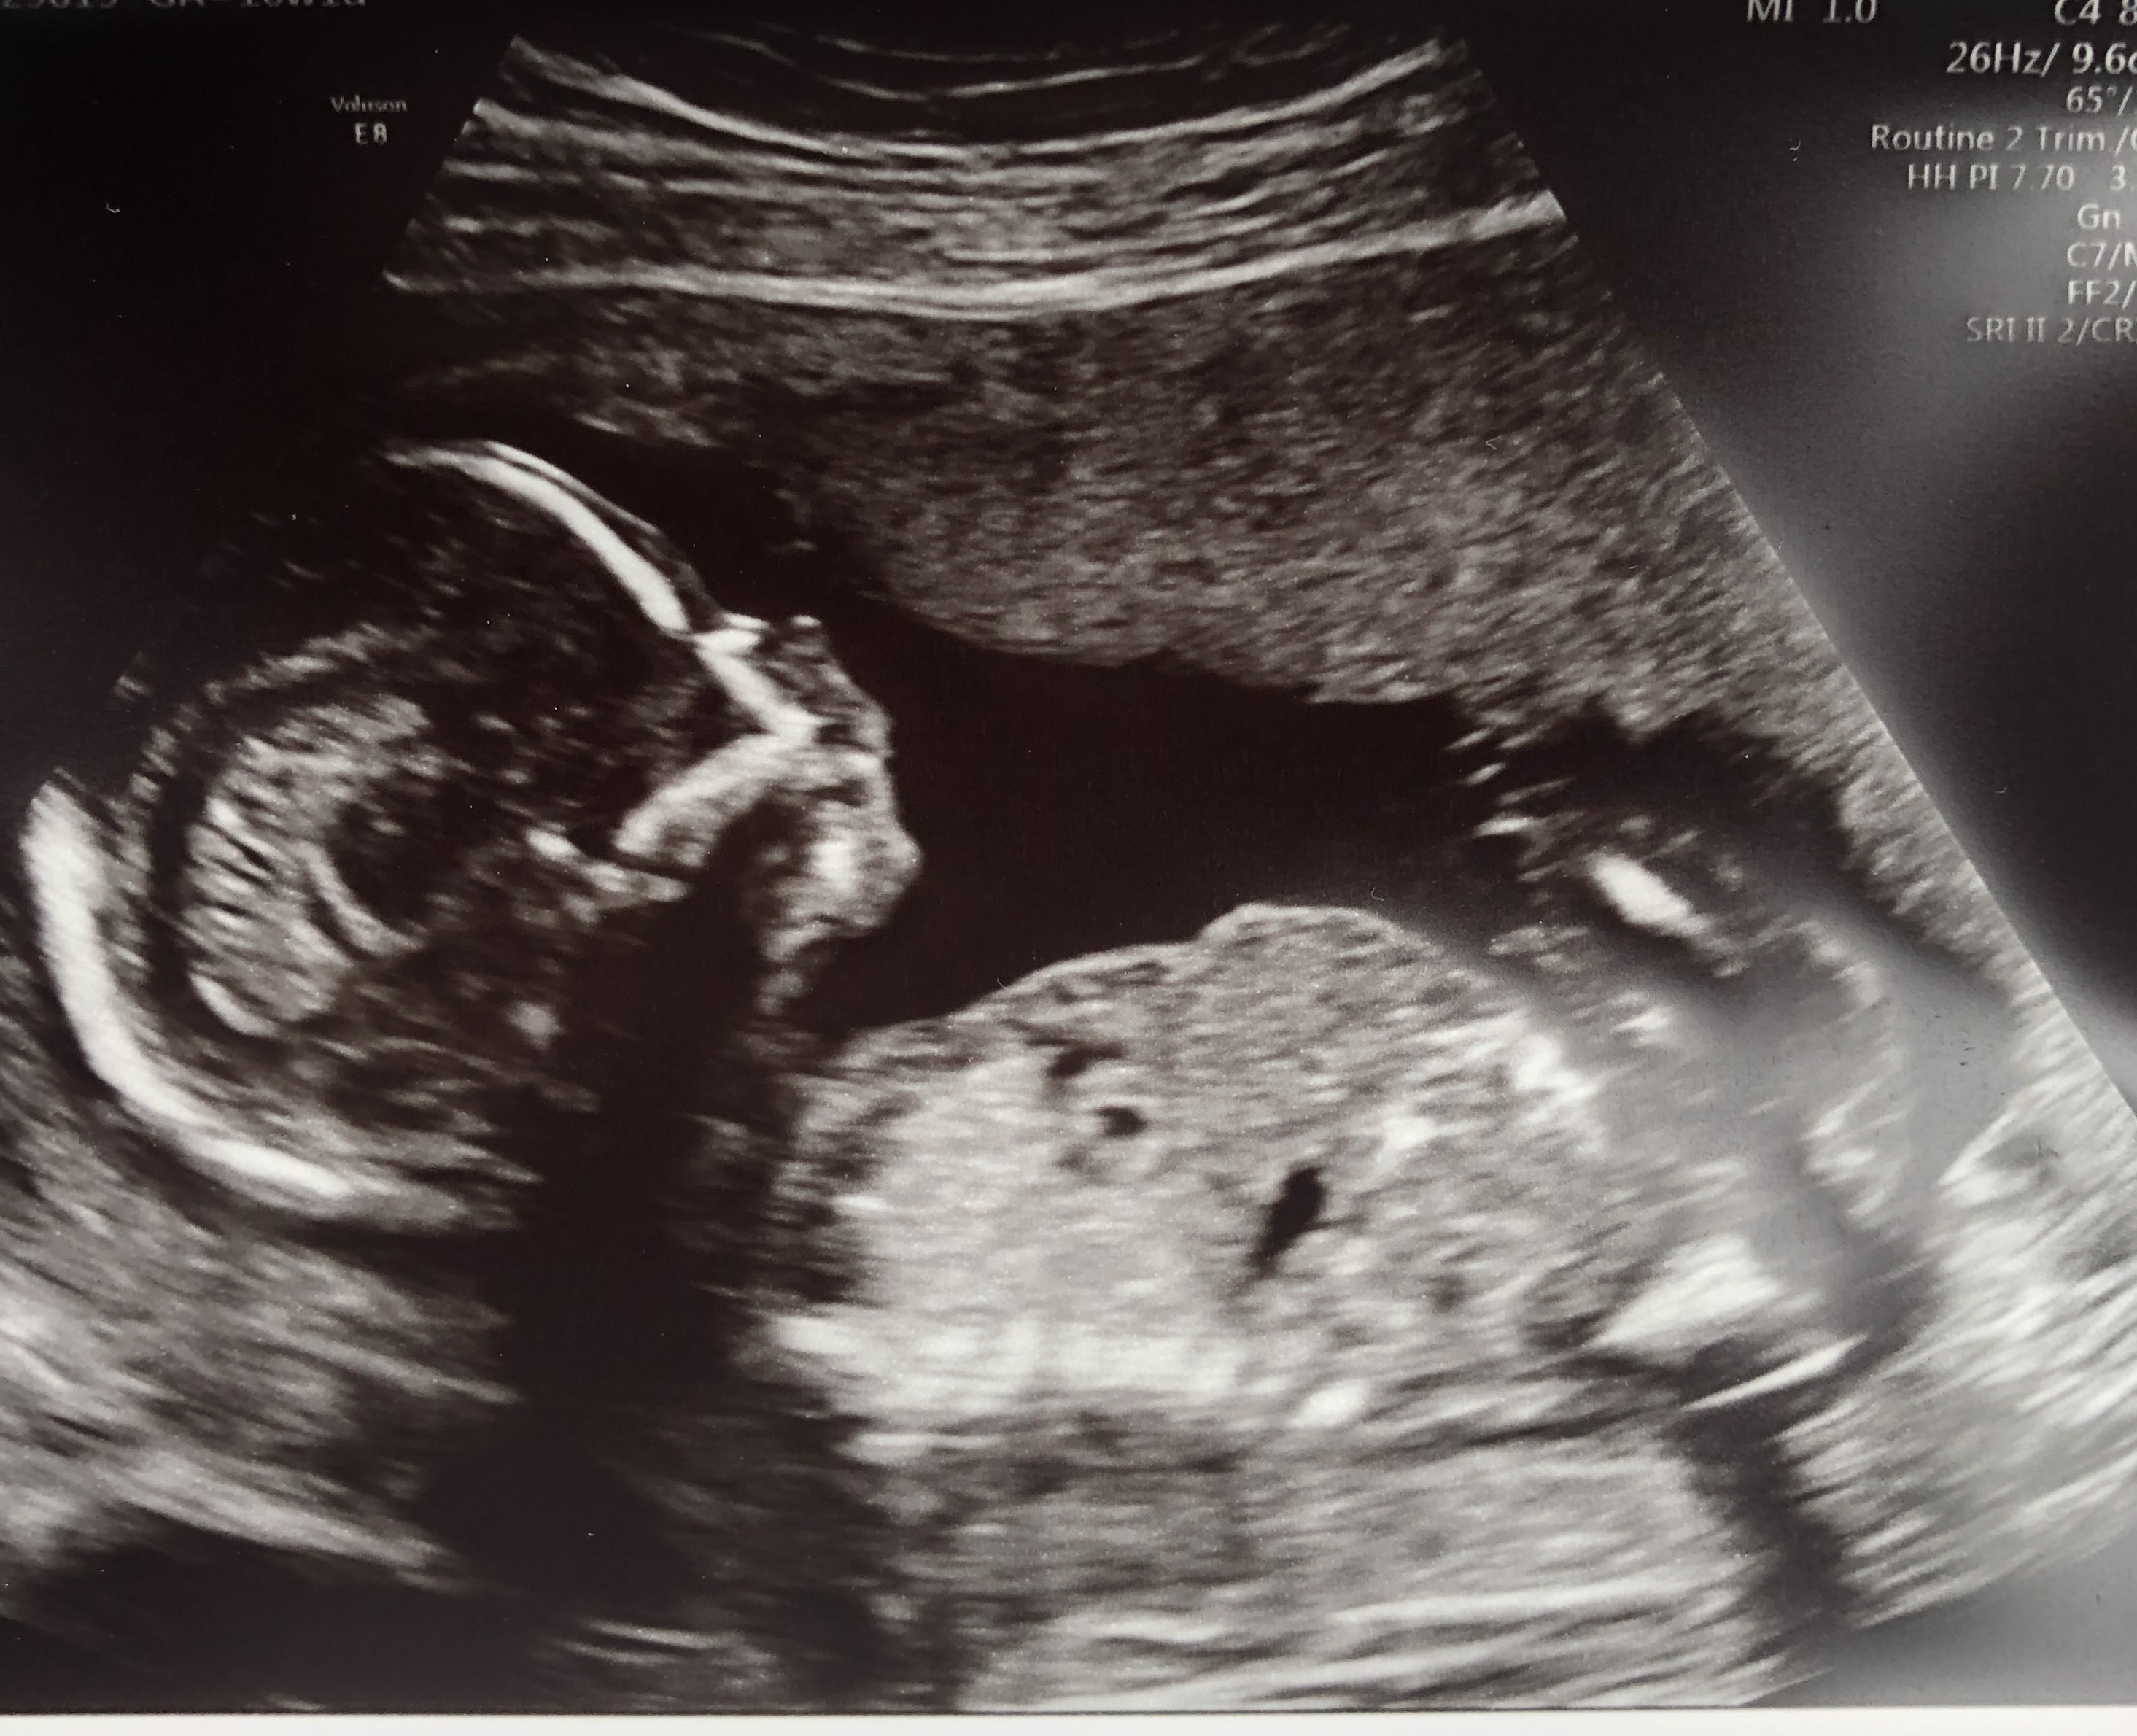

I’m not sure if there’s any sign of a nub in either picture, but here’s my scan at 12 weeks.

Have also included my 16 week scan pic just in case! Attachment 41945Attachment 41946Attachment 41947

Yes I"m afraid they're just not the best shots for guessing. Possibly pink lean but I have low confidence in my guess.

This is difficult. I thought it was a girl based on first and second shot (but hard to see if it is the nub).